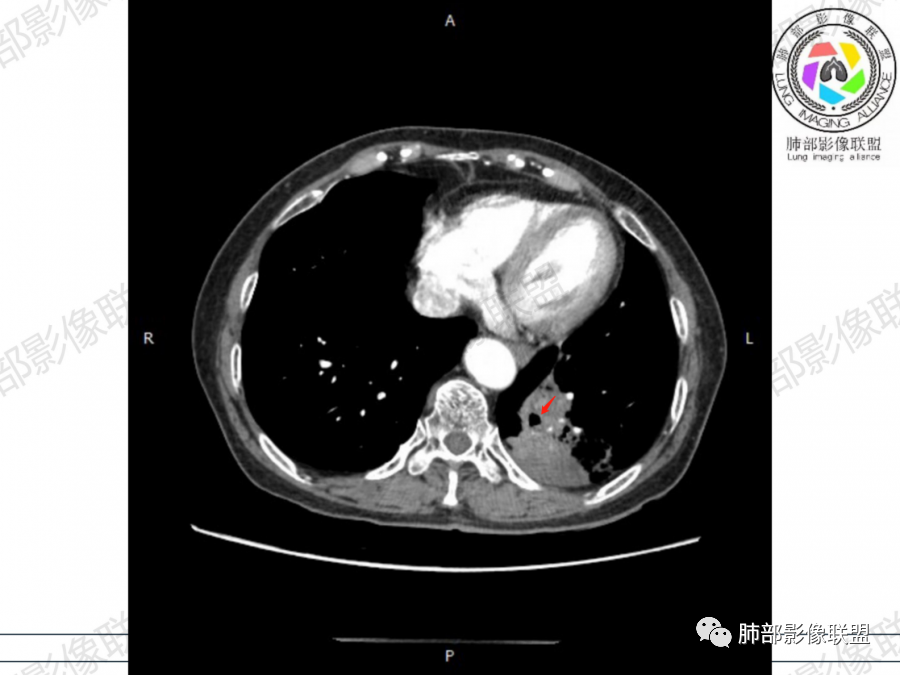

晨读病例,老年人男性 左肺下叶病灶,实性病变加上边界清晰的磨玻璃影,实性病变可见明显的膨胀性生长,增强实性部分可见血管照影征,考虑腺癌,粘液腺癌可能。

左肺下叶胸膜下混合磨玻璃影,磨玻璃边界清晰,支气管进入后堵塞,增强轻中度强化,无明显坏死空洞。

空腔+铺路石征+边界清楚GGO+病灶内血管局部扭曲+强化不均匀+病史长,指向腺癌,特别是粘液腺癌

晨读:左肺下叶胸膜下实性高密度影,部分伴有网格样增厚,内部可见小空泡,壁光滑,周围伴有磨玻璃影,边界清,近端可见支气管穿行,远端支气管堵塞,胸膜下脂肪间隙可见,病变整体收缩,部分有彭隆,增强后可见血管穿行,强化尚均匀。

临床:慢性咯血,无发热等感染症状,实验室血象不高,考虑:粘液腺癌,鉴别:慢性脓肿,结核,炎性假瘤

左肺下叶实变及磨玻璃影,宽基底与胸膜相远,磨玻璃边界清晰,边缘膨隆,病变内近端支气管堵塞,不均匀强化,可见血管影,考虑腺癌,鉴别结核

晨读:老年男性,72岁,咳嗽咯血一月,加重一天。细胞角蛋白19片段增高。

胸CT:左下叶胸膜下大片斑片影,长轴沿胸膜分布,实变、GGO混杂,磨玻璃边界清晰,粘液密度,小叶内间隔增厚,支气管进入后堵塞(枯枝),增强轻中度强化,血管造影征。常规考虑:肺腺癌?淋巴瘤?鉴别不典型病原体感染。

2、影像表现:无肺气肿背景,病变定位于左肺下叶背内侧基底段,病灶呈不规则团块影,靠近胸膜侧,其内密度不均匀,内见空洞、实变及磨玻璃影,磨玻璃影呈碎石路征,边界清楚,实性肿块边界膨隆,其内见空洞。空洞周围比较实。病灶较大的支气管通畅,细小的支气管成“枯枝征”。无胸膜增厚及胸膜腔积液,增强扫描呈中度强化,见血管造影征。